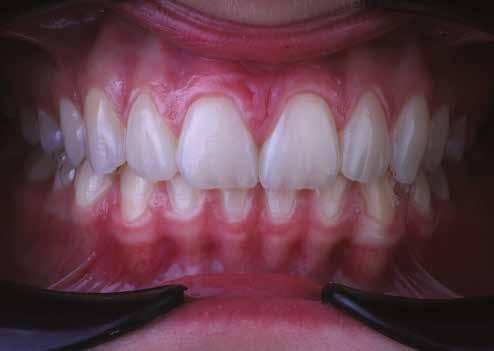

A fogászati kezelések során manapság már nem kizárólag az esztétikai megjelenés helyreállítására törekszünk. Sokszor a kedvezőtlen esztétikai megjelenés hátterében álló okok következményes módon a fogazat funkcionális működését is károsítják, így a kezelések során ezeknek a helyreállításával is foglalkoznunk kell. A különböző funkcionális és esztétikai diszkrepanciák kezelésére számtalan módszer létezik, ám ezen fogászati beavatkozások mindegyikében közös, hogy a kivitelezésük során nagyon szoros együttműködésre van szükség a kezelést végző fogorvos és a munkáját segítő fogtechnikus között. Az alábbi esetbemutatás során egy fiatal hölgypáciens fogazatának héjak alkalmazásával történő esztétikai és funkcionális rehabilitációját szeretnénk ismertetni.

Esetbemutatás

A 19 éves hölgypáciens azzal a kéréssel jelentkezett a rendelőnkbe, hogy szebb fogakat szeretne. Az első konzultáció alkalmával megkérdeztük, hogy mi zavarja leginkább a fogazatának jelenlegi megjelenésében, valamint azt is megbeszéltük vele, hogy milyen végeredmény elérése esetén lenne maradéktalanul elégedett. Ebben az esetben a kezelési célokat az alábbiakban határoztuk meg:

A páciens fogazata esztétikai megjelenésének és funkcionális működésének a lehető legtöbb, saját foganyag megtartása mellett történő helyreállítása (1. és 3. ábra). A lehető legideálisabb esztétikai végeredmény elérése érdekében néhány esetben a fogak alakjának módosítá -

sára is szükség van (2. és 4. ábra).

A kezelés megtervezése során kifejezett jelentősége van annak, hogy jó kommunikáció legyen a páciens, a fogorvos és a fogtechnikus között. A páciens leendő fogazatának természetes megjelenését a kezelésben részt vevő team szakmai felkészültsége, gyakorlati tapasztalata és a kezelés sikerességének irányába történő elkötelezettsége biztosítja. A beavatkozások megkezdése előtt megtörtént a páciens anamnézisének a felvétele, valamint a klinikai kivizsgálását is elvégeztük. Ezt követően lenyomatokat készítettünk a kiindulási állapotról, majd a kiindulási helyzetet extra- és intraorális fotók segítségével is rögzítettük (13. a-c. ábra).